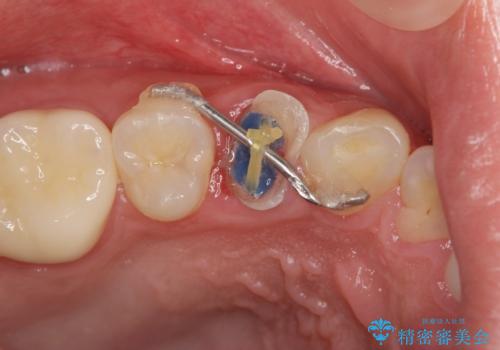

今回は虫歯の深いところが歯茎のラインにくるまで部分矯正で引っ張り出し、適合の良いかぶせ物を装着しました。

初診時の状態では虫歯が大きすぎて取り切ることができなかったため、まず歯を骨から引きあげて虫歯がしっかり除去できる状態にしました。

虫歯を取り切った後は、歯を引きあげたことで一緒に上がってきてしまった骨をならしていきます。

その後ラバーダムをして根っこの治療をし、被せ物を被せて治療終了となりました。